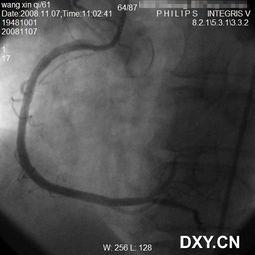

首先,得先了解一下什么是雷帕霉素支架。雷帕霉素是一种抗生素,而雷帕霉素支架则是将这种药物包裹在支架表面,用于治疗冠状动脉狭窄。这种支架在2000年左右问世,因其独特的药物涂层,在心血管领域引起了广泛关注。

在雷帕霉素支架刚问世的时候,由于技术壁垒较高,全球市场几乎被进口品牌垄断。其中,美国的Cypher支架和德国的Taxus支架是当时市场上的佼佼者。这些进口支架凭借其优异的性能和稳定的疗效,赢得了广大医生和患者的青睐。